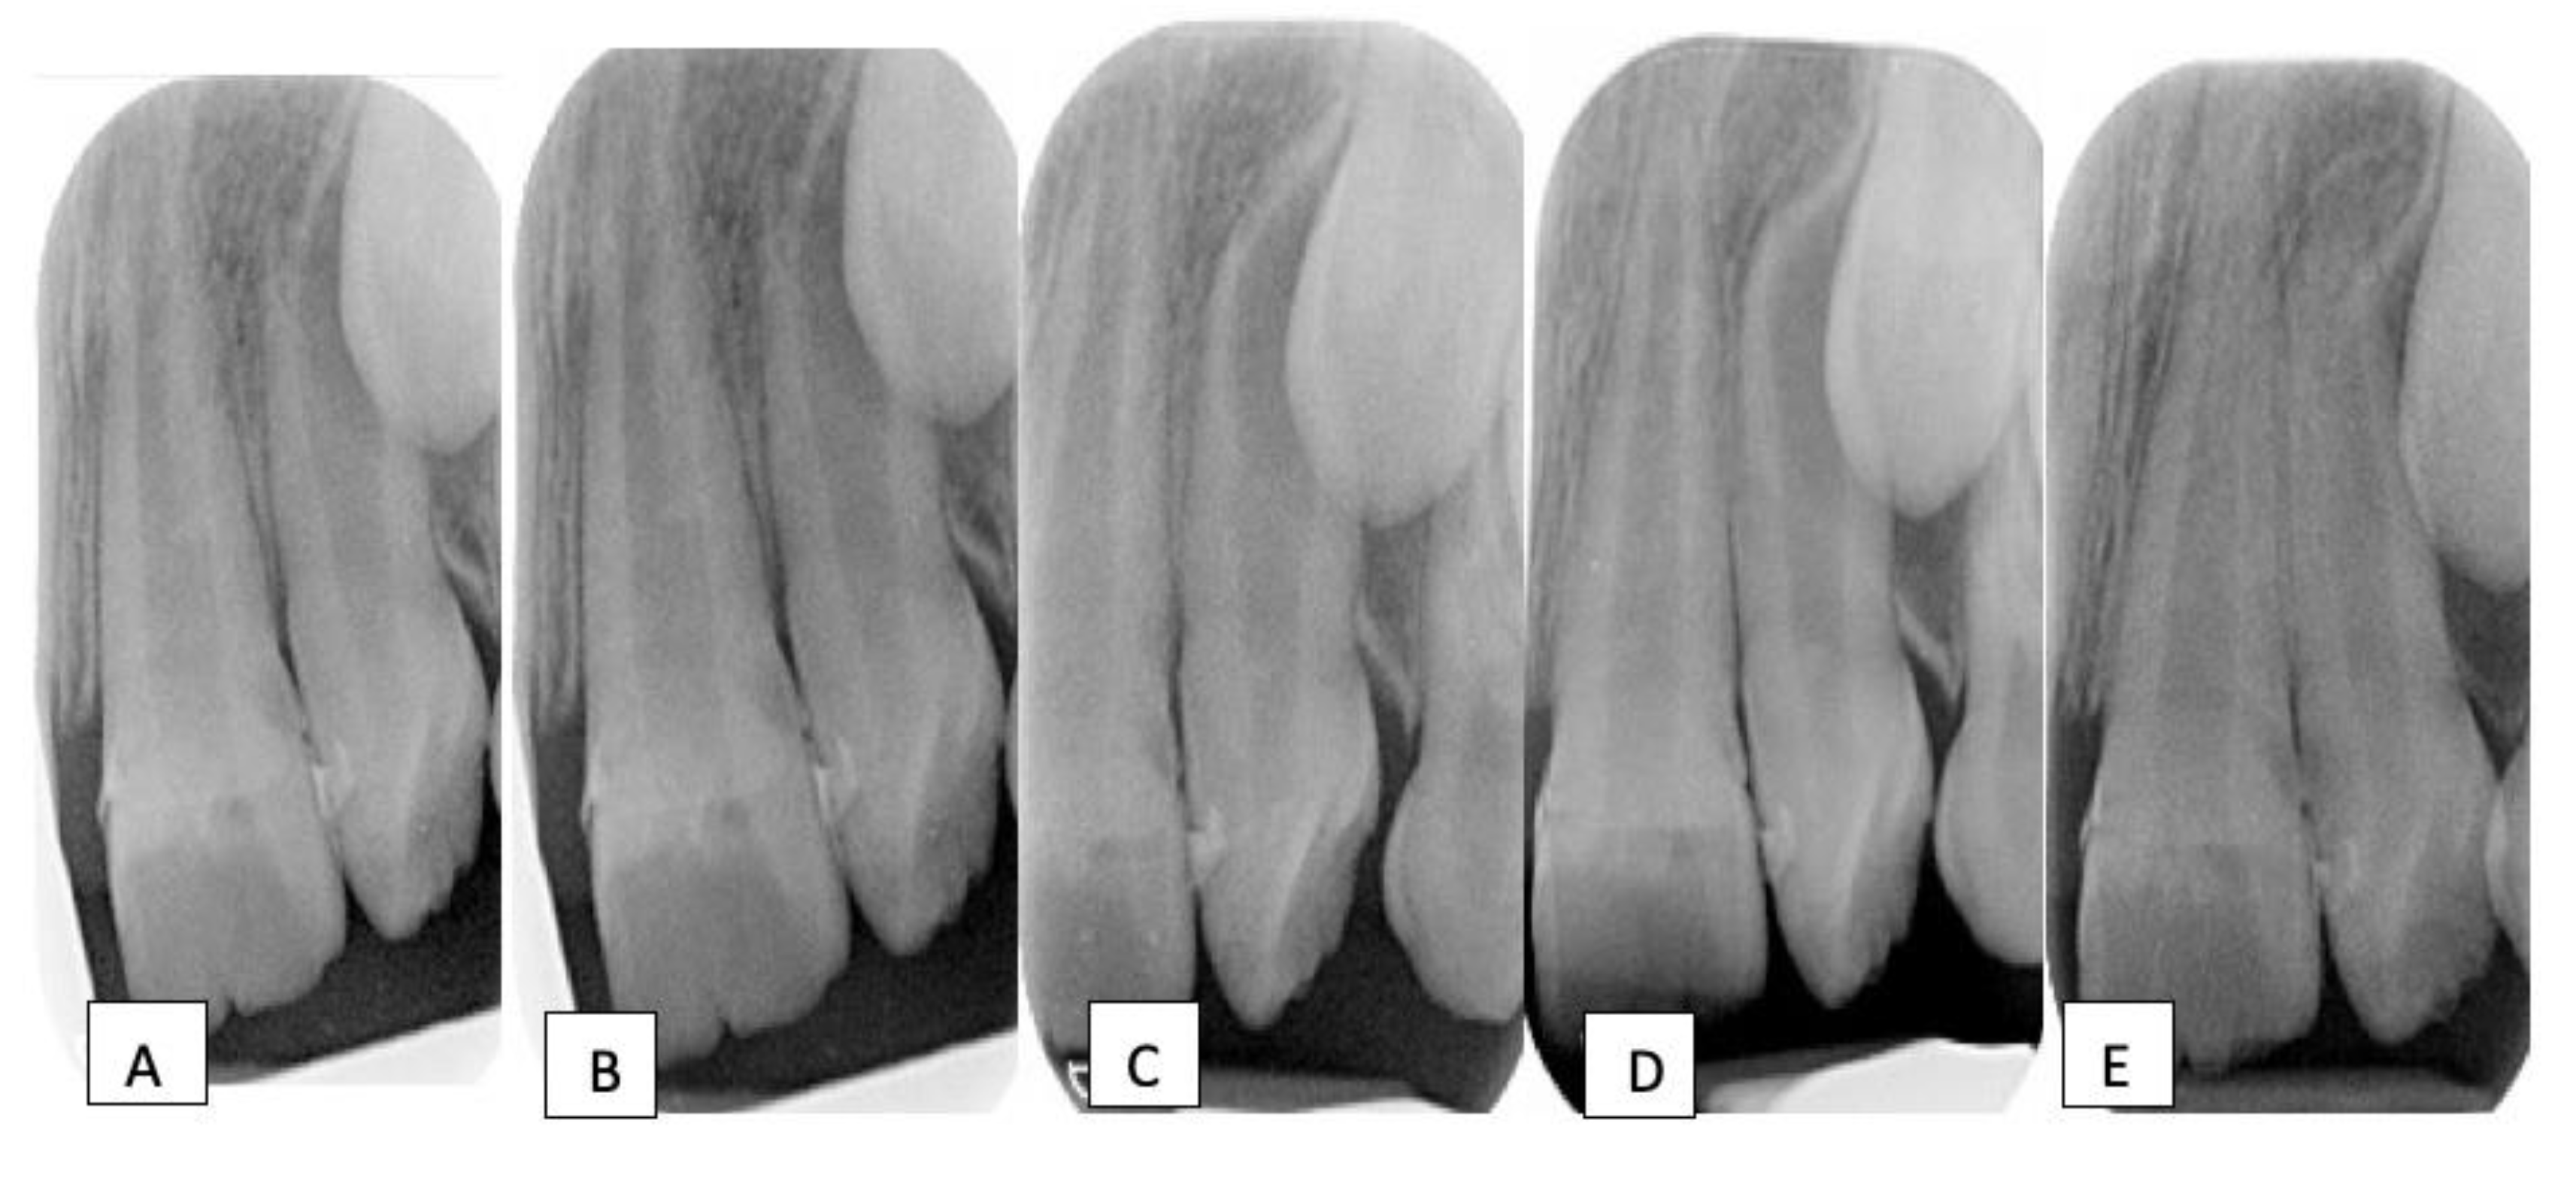

At the postoperative review (2 weeks after the surgery), there was a satisfactory healing with a complete resolution of the sinus tract. The periodontal examination showed resolution of the increased probing depths. The patient was then placed on a 3-monthly recall interval to monitor the development and eruption of the upper left incisors. Owing to the hypoplastic enamel defects, intermittent sensitivity later developed in the upper left permanent incisors, and desensitizing agents (e.g., tooth mousse) were used and oral hygiene instructions were reinforced. Nevertheless, a normal eruption rate of these incisors with appropriate root formation and satisfactory apical closure was evident on subsequent follow-up visits, confirming pulp vitality and favorable outcomes in these teeth [13] (Figure 4).

Figure 4.

Radiographic evaluation of 11 & 21; (A) 2 weeks after the surgery (immediate post-operative review), (B) at 3-month, (C) at 6-month, (D) at 12-month, (E) at 24-month recall visits. Notice the continued root development and the apical closure in the hypoplastic teeth.